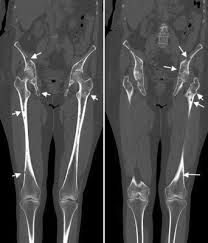

3 Radiologische Diagnostik Des Multiplen Myeloms 3 3 Radiologisch Pathologische Korrelation